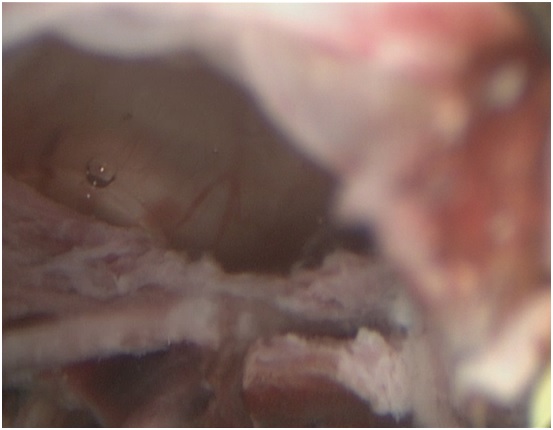

Произведена гистерорезектоскопия под контролем лапароскопии. При гистероскопии сразу за внутренним зевом в области рубца по передней стенке выявлена «ниша» 3,0*2,0*1,0 см, выполненная темными сгустками крови и остатками хориальной ткани (см. рисунок №1). Петлей резектоскопа в биполярном режиме в «нише» удалена патологическая ткань (см рисунок №2). Гистологически подтверждено наличие ворсин хориона, элементов трофобласта.

Рис. 2. Несостоятельность рубца на матке

«Ниша» в области п/о рубца на матке